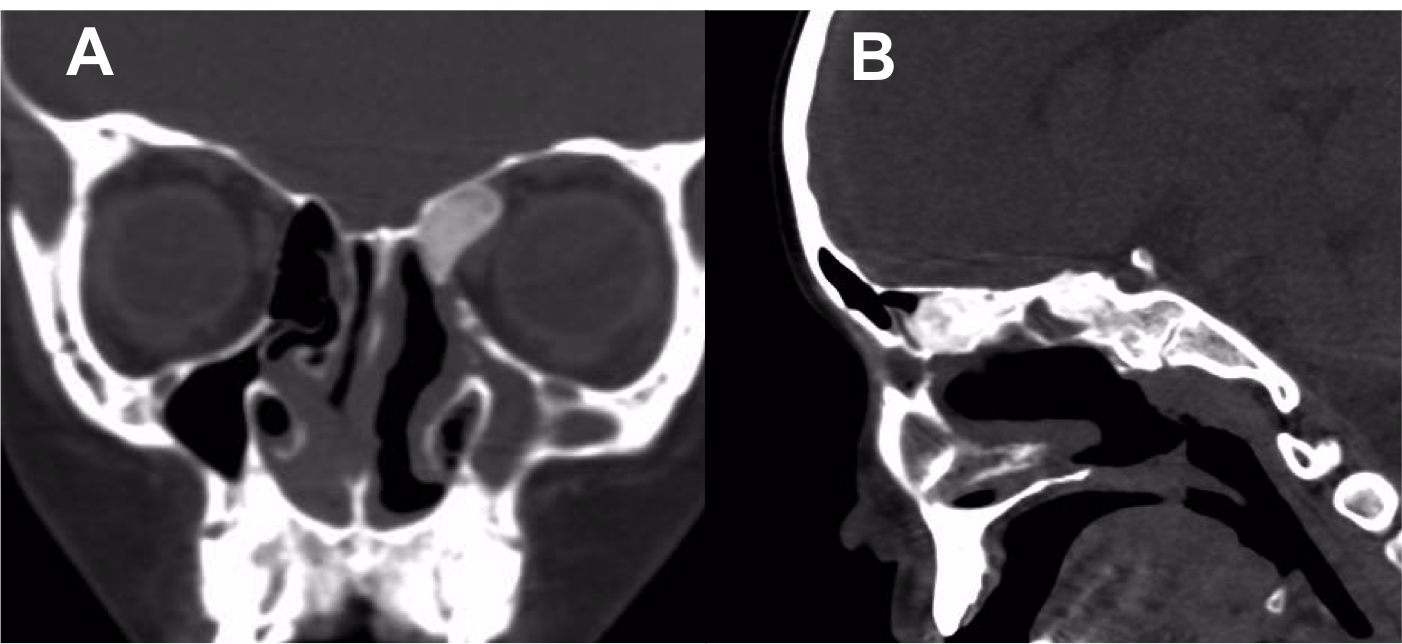

Introducción: La cirugía endoscópica endonasal se ha convertido en una herramienta fundamental para el manejo de patologías que comprometen la base de cráneo. En casos bien seleccionados, estas técnicas permiten resecciones quirúrgicas con una menor morbilidad sin comprometer los principios oncológicos de resección. Con el desarrollo de instrumental especializado, nuevas tecnologías y la experiencia de los cirujanos, la cirugía endoscópica endonasal se usa cada vez más en cirugía de base de cráneo en niños.

Objetivo: presentar una serie de casos de pacientes pediátricos con tumores de base de cráneo manejados con cirugía endoscópica endonasal.

Diseño: Estudio observacional descriptivo de tipo serie de casos. Metodología: se describe la experiencia con pacientes pediátricos llevados a cirugía endoscópica endonasal para manejo de tumores de base de cráneo en el Instituto Nacional de Cancerología entre julio de 2014 y diciembre de 2016.

Resultados: Fueron intervenidos 8 pacientes entre los 2 y 14 años, con una edad promedio de nueve años y un seguimiento promedio de 16 meses. En el 75% se hizo una resección total del tumor. Un paciente requirió una reintervención y un paciente fue sometido a radiocirugía post-operatoria. 1 paciente falleció a pesar de múltiples intervenciones, quimioterapia y radioterapia.

Conclusión: La cirugía endoscópica endonasal para tumores de base de cráneo puede ser utilizada de forma segura en los pacientes pediátricos, es una técnica que en casos bien seleccionados pueden ofrecer excelentes resultados disminuyendo la morbilidad y complicaciones de las técnicas abiertas.